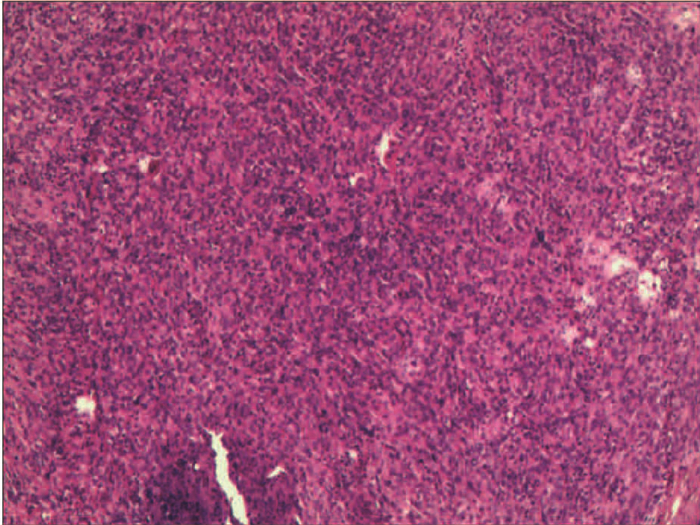

Clinical and pathological features of progressive familial intrahepatic cholestasis type 3

Yuhang WENG, Qingfang XIONG, Duxian LIU, Xulei ZHANG, Yongfeng YANG

2022, 38(1): 154-159. DOI: 10.3969/j.issn.1001-5256.2022.01.024

Abstract(1849) HTML (765) PDF (2621KB)(143)

Abstract:

Objective  To investigate the clinical and pathological features of progressive familial intrahepatic cholestasis type 3 (PFIC3).  Methods  A retrospective analysis was performed for 1326 patients with unexplained liver disease who attended Nanjing Second Hospital from January 2017 to December 2019, among whom 8 patients were diagnosed with PFIC3 based on clinical/pathological manifestation and gene sequencing results (1 patient did not undergo liver biopsy due to contraindication). Clinical, laboratory, imaging, and pathological findings were analyzed and a literature review was performed for the pathology of ABCB4-related diseases to summarize the clinical and pathological features of PFIC-3.  Results  Among the 8 patients with PFIC3, there were 5 male patients and 3 female patients, with a median age of 29.5 years. Of all 8 patients, 4 (50%) manifested as chronic cholestasis and 4 (50%) manifested as biliary cirrhosis, among whom 3 (75%) had the manifestation of portal hypertension. As for biochemical examination, 75% (6/8) had an increase in alkaline phosphatase, and 100% (8/8) had an increase in gamma-glutamyl transpeptidase. As for imaging examination, 50% (4/8) had cholecystitis, 25% (2/8) had gallstones, 25% (2/8) had bile duct dilatation, 75% (6/8) had splenomegaly, and 25% (2/8) had liver cirrhosis. As for liver biopsy, all 7 patients manifested as bile duct injury and/or reduction, and 57.1% (5/7) had absence of the bile duct. Multidrug resistance P-glycoprotein 3 (MDR3) immunohistochemical staining showed normal expression in 42.9% (3/7) of the patients and reduced expression in 57.1% (4/7) of the patients. Literature review obtained 17 articles with a description of the bile duct or MDR3 immunohistochemistry. Among the 7 patients with low phospholipid-associated cholelithiasis, 71.4% (5/7) had normal bile duct, 14.3% (1/7) had bile duct reduction, and 14.3% (1/7) had absence of the bile duct; among the 6 patients with intrahepatic cholestasis of pregnancy, 16.7% (1/6) had normal bile duct, 50% (3/6) had bile duct reduction, and 33.3% (2/6) had absence of the bile duct; among the 8 patients with PFIC3, 25% (2/8) had bile duct reduction and 75% (6/8) had absence of bile duct; among the 21 patients with PFIC3, 9.5% (2/21) had normal expression of MDR3, 23.8% (5/21) had a reduction in the expression of MDR3, and 66.7% (14/21) had absence of the expression of MDR3.  Conclusion  PFIC3 mainly manifests as cholestasis, cholelithiasis, and hepatic fibrosis. Pathological manifestation includes bile duct injury and bile duct reduction or absence of the bile duct in severe cases, and the degree of injury is associated with disease severity. MDR3 immunohistochemistry may show normal expression, reduced expression, or absence of expression, and diagnosis cannot be excluded in patients with normal expression. Genetic testing can be performed for diagnosis when necessary.